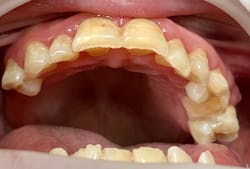

Katie presented with multiple areas of dental decay, heavy plaque buildup, and light to moderate supragingival calculus with little subgingival calculus. There are signs of bruxism with wear and small fractures on her teeth (figures 1 and 2). Katie has a large tongue that often covers her teeth while her mouth is open (figure 3). She has an anterior and posterior crossbite (figure 4) and a retained primary tooth. Katie was cooperative for radiographs, which were taken while working with her verbally and using positive wording and demonstrations. Extra time was taken to allow her to process what was being described and to abate her fears.